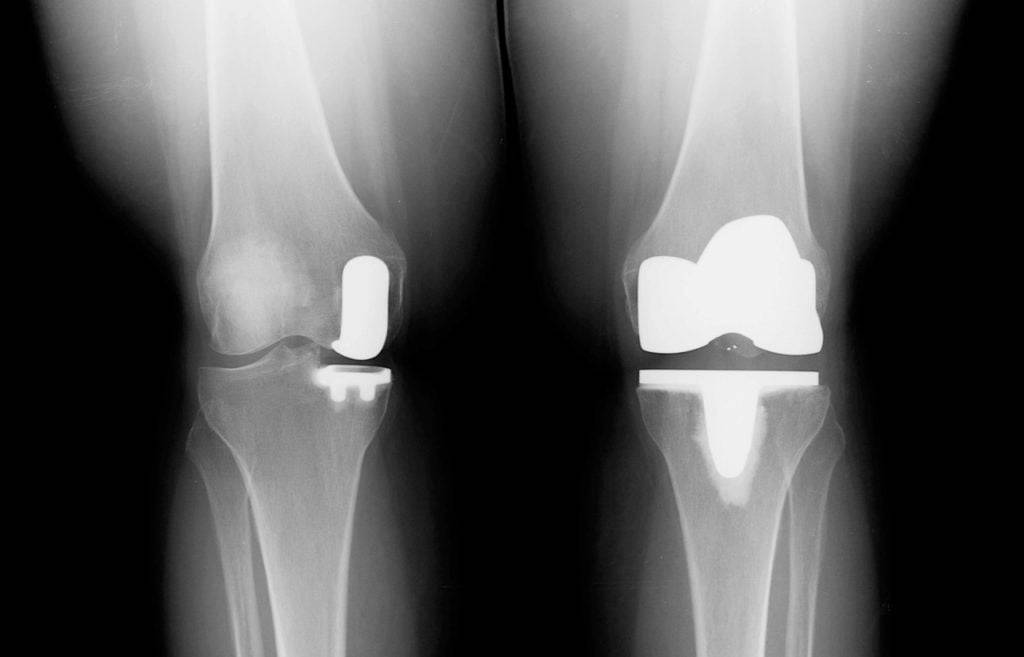

Разновидность импланта для частичного эндопротезирования коленного сустава.

Взгляд на имплант изнутри.

На фото — две ноги одного пациента: слева операция была проведена частично, справа — полностью.